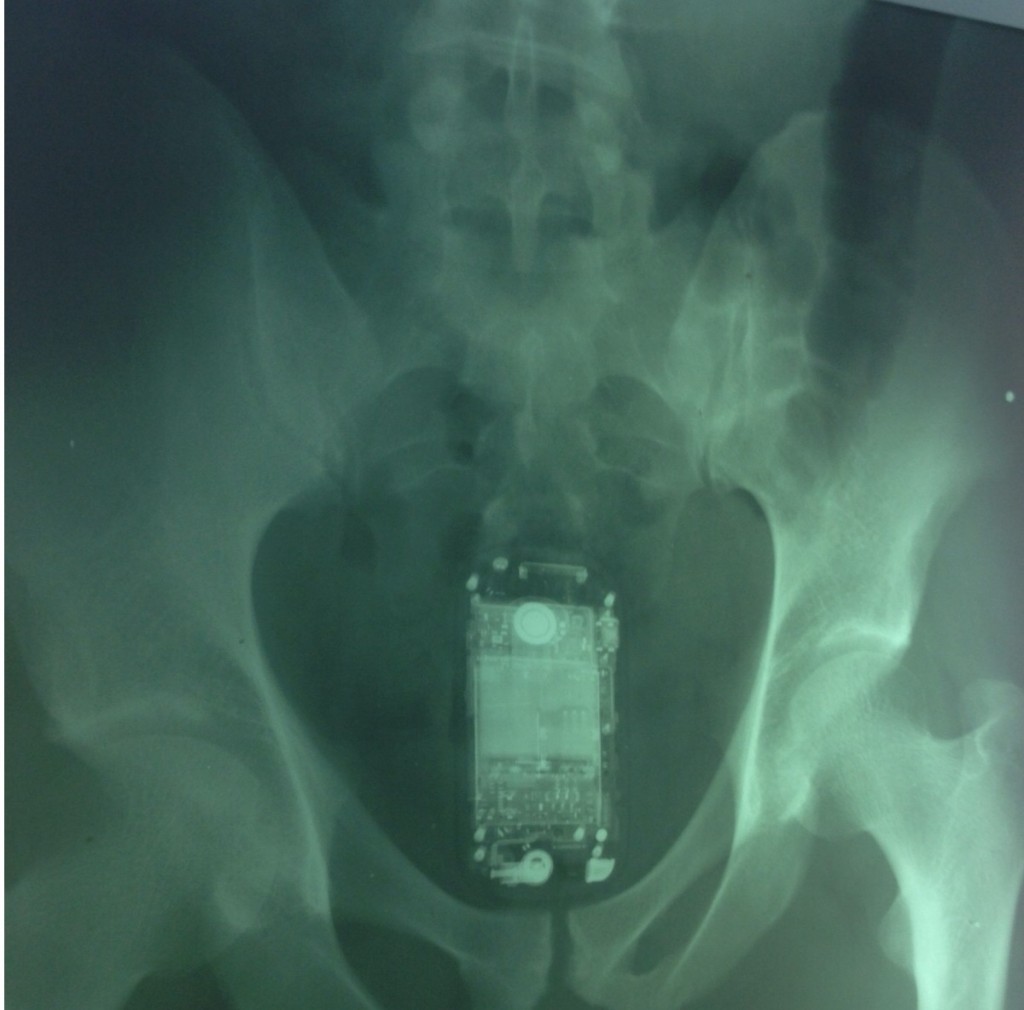

Detento esconde celular no ‘ânus’

Um detento identificado como Fabrício Melo B. Silva foi flagrado nesta semana na Unidade Prisional da cidade de Timon, no Maranhão, com um aparelho de celular smartphone escondido no ânus.

“O preso tinha escondido o aparelho telefônico dentro dele e depois que foi descoberto retirou da parte intima”, disse o funcionário, que não diz se identificado.

A tentativa frustrada foi descoberta pelos agentes penitenciários que utilizam detectores de metais durante uma revista de rotina.